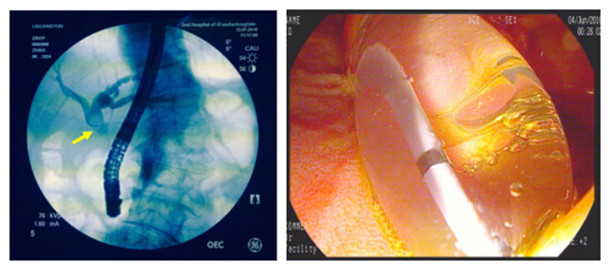

2016年7月13日,由赵刚主治医师操作,在左爱丽护士长、李婵护士、杨龙宝博士的协助下,在密切监护患者生命体征的同时对其实施ERCP手术。术中可见患者十二指肠降部有多发巨大憩室,十二指肠乳头位于其中一憩室内,属于憩室内乳头的情况,操作稍有不慎即可能引起十二指肠穿孔。一次性顺利插管至胆总管并造影,确认了胆管中结石的大小约1.2cmx1.4cm,位于肝总管处(结石可能由于插管及造影发生了位移),同时也发现由于憩室的压迫,患者胆管走形异常扭曲。我们对该患者的十二指肠乳头进行了小切开并以1.2cm胆管扩张球囊进行扩张,后以取石球囊顺利自胆管中取出巨大成型结石一枚,再次造影胆管内未见残存结石,遂置入鼻胆管,整个操作过程用时仅30分钟。患者术后第2天即恢复正常饮食,腹痛症状基本消失,目前已经顺利出院。

造影可见结石位于肝总管处(黄箭头所示) 胆道扩张球囊进行扩张的过程